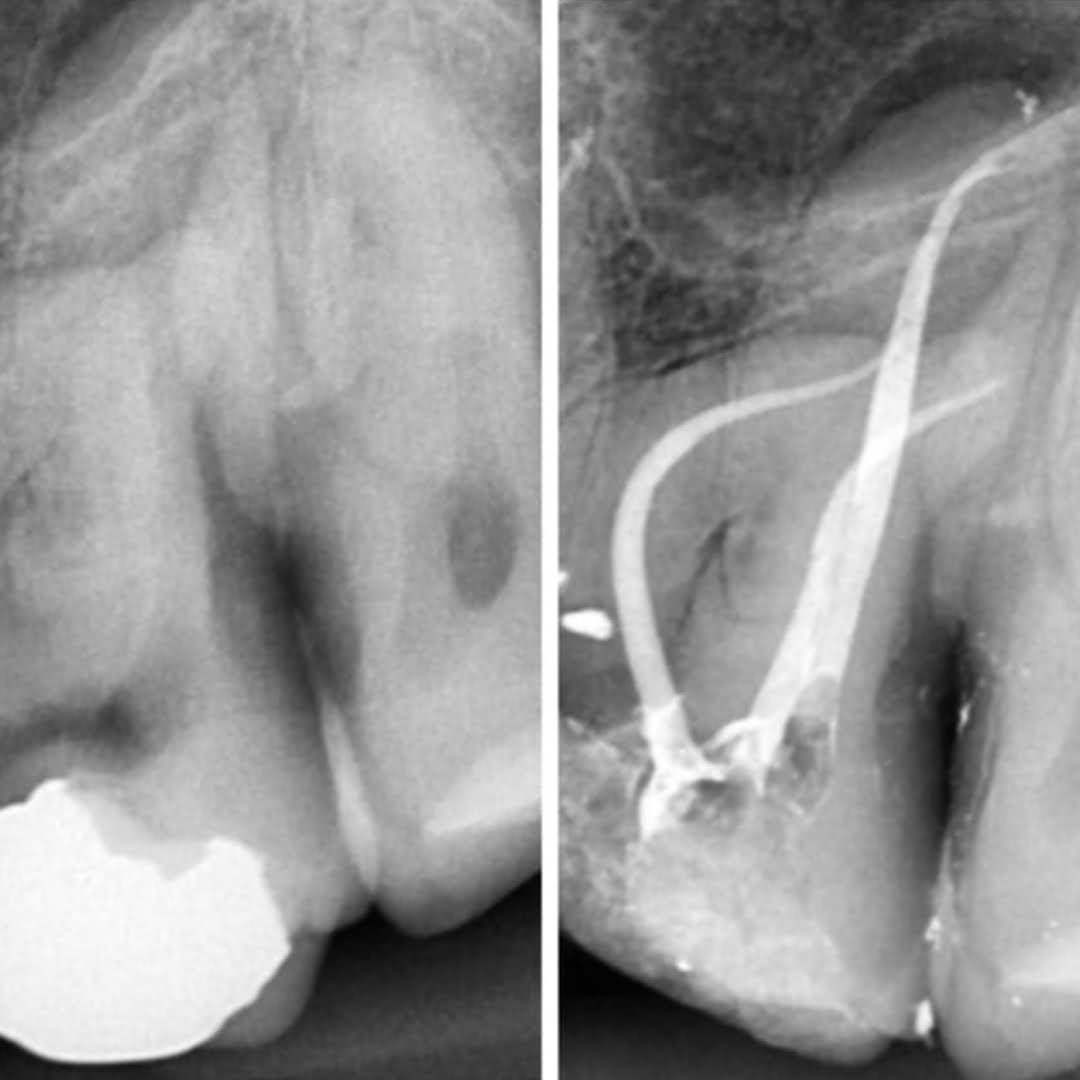

A Endodontia, mais conhecida como Canal, é um tratamento para dentes danificados por uma grande cavidade. A Endodontia é indicada quando a polpa dentro do canal radicular fica inflamada e infectada.

O procedimento funciona criando um pequeno orifício no dente para que todas as áreas infectadas possam ser removidas. A polpa dentária é removida e, muitas vezes, para prevenir a propagação da infecção, as raízes também são removidas.

Uma vez feito isso, a área é limpa para garantir que a infecção tenha desaparecido. Normalmente antibióticos são prescritos. Isso garante que qualquer infecção persistente seja eliminada.

Para um diagnóstico preciso e acompanhamento da evolução do seu tratamento.